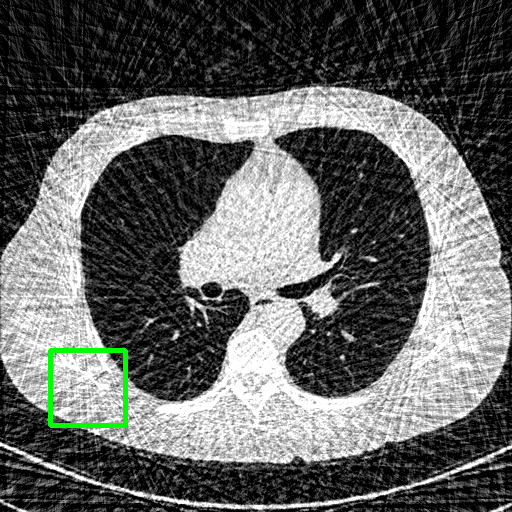

Qualitative comparison. We also visualize the reconstructed images of these methods in Fig. 4 with = [72, 96 ,144] (See more visualizations in Appendix). In all three rows, our DuDoTrans shows better detail recovery, and sparse-view artifacts are suppressed. Further, when decreasing , where raw sinograms are too messy to be restored and low-quality images from FBP are too hard to capture global features, Transformer-based models exhibit reduced performance. The phenomena suggests that we should design suitable structures with the Transformer and CNNs, facing with different cases.

Ground Truth

FBP

FBPConvNet

DuDoNet

ImgTrans

DuDoTrans